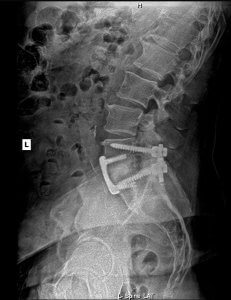

Below, you’ll see Jeff’s X-rays, taken when he first began care and again just four months later. Jeff has a medical fusion in his lower spine, yet under chiropractic care, his body adapted beautifully. Not only did he regain movement, energy, and the ability to enjoy activities like walking a full 18 holes of golf pain-free, but we also saw meaningful structural changes in his spine, including improved alignment, disc spacing, and restoration of his natural lumbar curve.

Starting Care: Follow-Up Check: